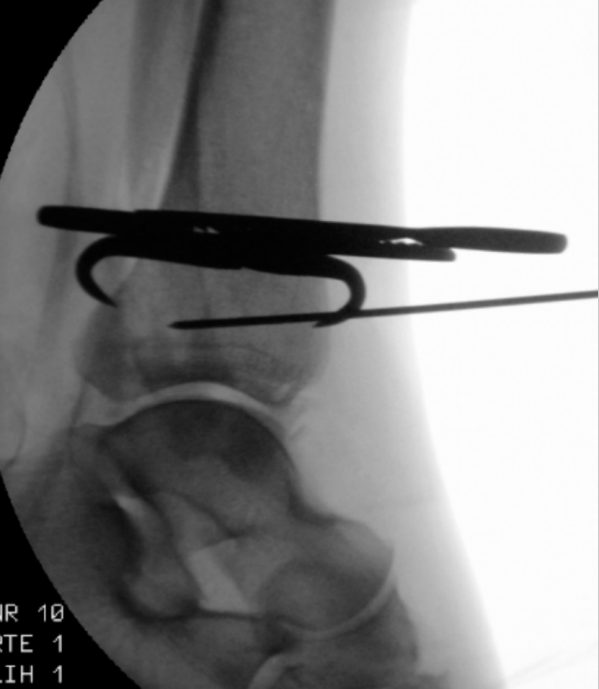

仔细行骨膜下剥离后,显露后踝骨折,清除嵌入的软组织,使用尖头复位钳进行解剖复位并临时固定(图3a)。确认复位满意后,于胫骨平台外侧三分之一、骨骺瘢痕近端确定导针进针点。此位置允许建立垂直于骨折平面的由后向前螺钉轨迹,从而在**化加压的同时避免关节内穿入。

经一长约1厘米的纵向皮肤切口,显露胫骨前侧皮质。在透视引导下,并使用两把小号Longbeck拉钩保护伸肌腱及神经血管结构,将一枚用于4.5毫米无头双螺纹加压螺钉的1.6毫米导针,从前内侧向后外侧、以约5-10°的向远端倾斜角置入(图3b–d)。经术中三维透视确认导针位置正确后(图3e),测量所需螺钉长度。

image.png

(a)

(b)

(c)

(d)

(e)

图3. (a–e): (a) 使用尖头复位钳临时固定;(b) 从前向后置入1.6毫米导针;(c) 踝穴位片,红线标记腓骨切迹后缘,蓝线标记前缘;(d) 点状末端视图证实轨迹位于切迹外;(e) 术中三维透视显示导针正确走行。